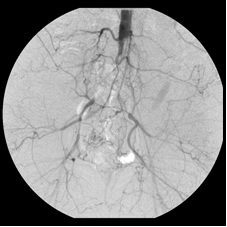

This 41-year-old woman smoked for a long time and developed severe bilateral calf cramping after short walks. Investigation revealed that she had completely occluded her distal abdominal aorta and her right and left iliac arteries, severely restricting the flow of blood into her lower limbs. She was unwilling to have surgery and came to me for minimally invasive treatment. By dripping urokinase (a clot dissolver) over 72 hours through two catheters that I advanced across the occlusions and later stenting the opened arteries, I wholly restored blood flow through her iliac channels. She walked again – without cramps.